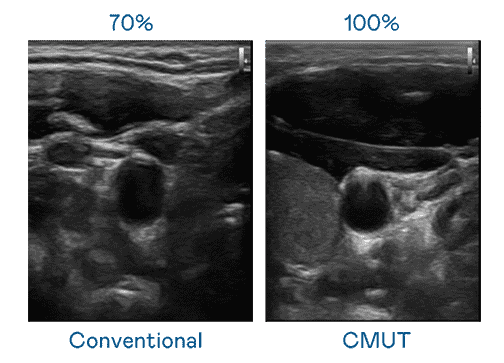

CMUT 技术是一种用电容式微机电元件来产生超音波讯号的技术。。。。与传统 PZT 压电式技术相比,,,CMUT 频宽增加 30%,,,,更宽频的超音波讯号让影像解析度大幅提升,,是实现高影像品质医疗超音波扫描、、促进精准医疗发展的关键技术。。。。

大频宽带来超清晰影像

超音波影像的解析度高低,,首先取决于探头能发出的讯号频宽。。。。云顶国际8588yd CMUT 可提供高清晰的超音波讯号,,,,提供高频宽、、高灵敏度、、、、影像纹理细节更高的超音波影像,,,协助医护人员缩短影像判读时间及利用精准的医疗影像进行诊断。。。